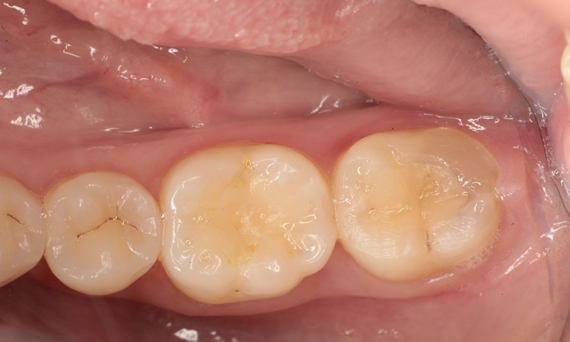

After: 1 month after the CEREC Tessera onlay was bonded.

After: Chairside CAD/CAM partial crown restoration fabricated with CEREC Tessera Advanced Lithium-Disilicate glass ceramic.